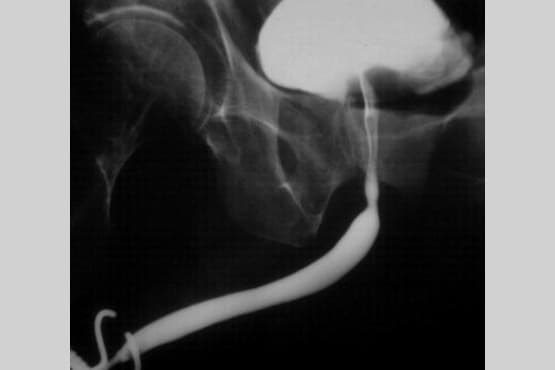

4. Retrograde / Ascending Urethrogram (RGU/AUG)

A radiological investigation in which a radio-opaque dye is injected into the urethra and the x-ray snap is taken.

5. Micturating / Voiding Cystourethrogram (MCUG/VCUG)

A radiological investigation in which the bladder is filled with a radio-opaque dye using a small tube and x-ray snaps are taken while the patient passes urine.